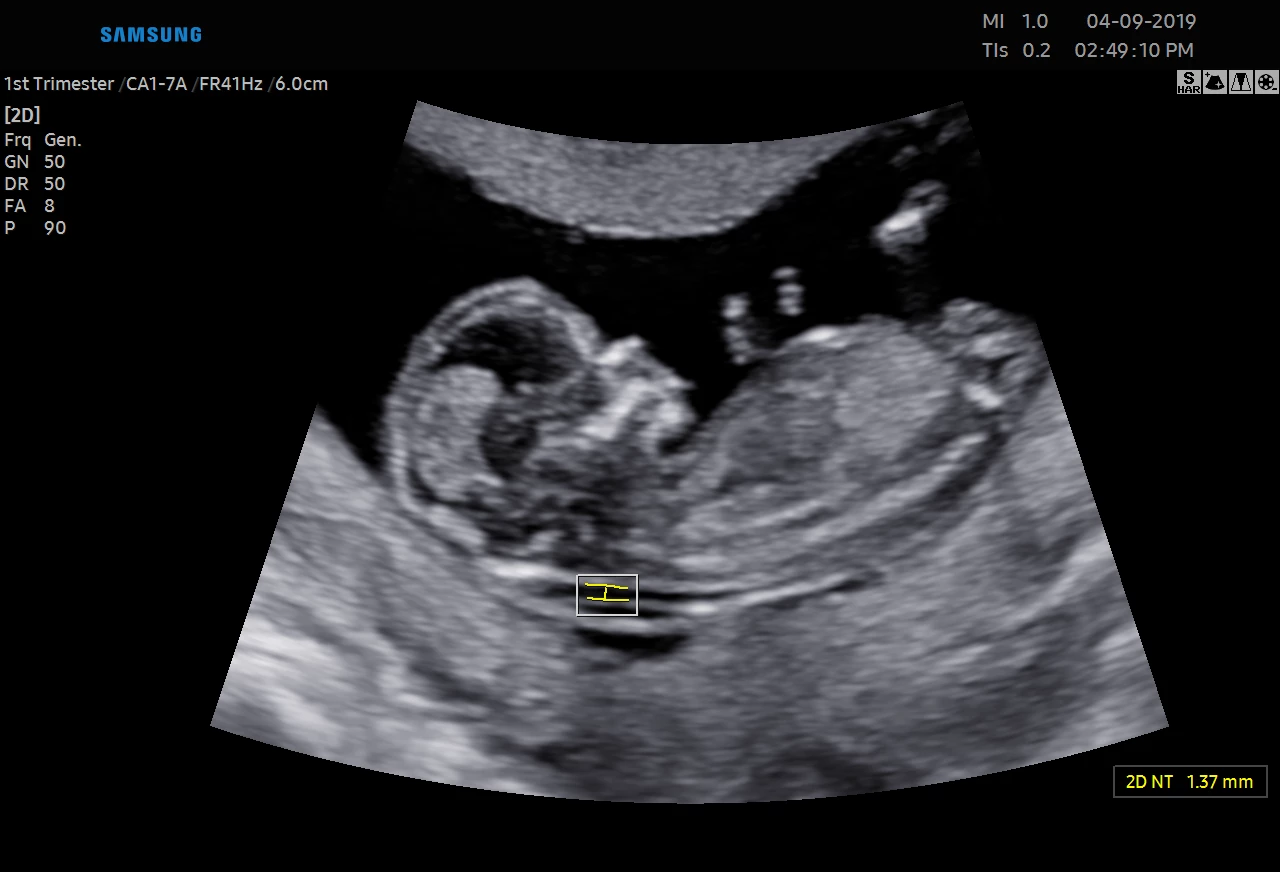

USG 3D dziecka w poradni ginekologicznej w Zambrowie –ocena NT, PAPP -A

Każdą kobietę w ciąży otaczamy kompleksową opieką, czuwając nad jej zdrowiem oraz prawidłowym rozwojem płodu. Podczas regularnych wizyt, zlecamy odpowiednie badania laboratoryjne. Korzystając z najnowszej generacji aparatu USG, przeprowadzamy bardzo dokładną diagnostykę obrazową – łącznie z USG 3D/4D płodu.